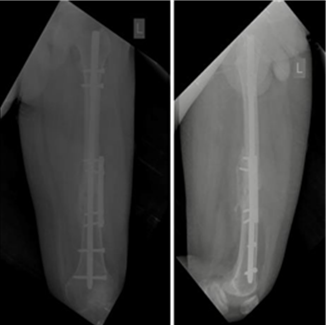

None of the patients experienced post-operative knee or hip stiffness after undergoing combination fixation with an intramedullary nail and derotation plate. X-rays of the patient with follow-ups at 3 months and 6 months(Fig. 1, 2, 3, 4).

Figure 4: POD 6-month X-rays.